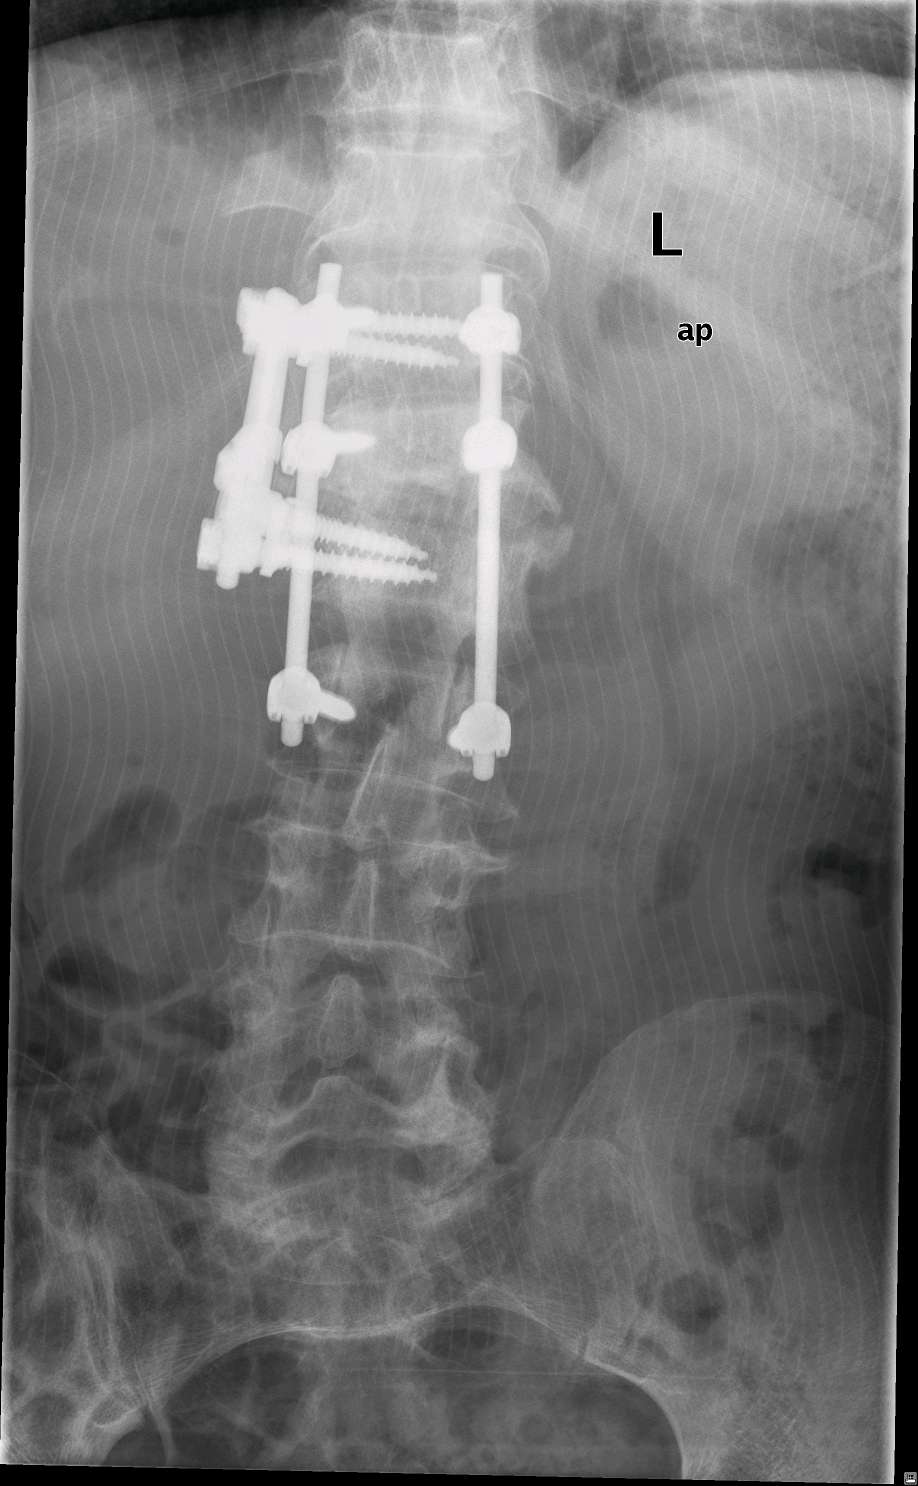

转到宝安区人民医院,经由张元豫主任医师诊断后,查T-spot阴性,c反应蛋白160,血沉89mm/h,是结核吗?如果不是结核,就是化脓性脊柱炎了,药物抗结核治疗3个月了,没有效果,应该就是化脓性脊柱炎了。不管怎么样,患者病情不允许再拖了,入院第三天行前后路病灶清除植骨融合术。术后使用万古霉素和莫西沙星后,患者C蛋白迅速降低。出院前c反应蛋白只有3,抗感染有效。

目前患者已经达到临床治愈出院。